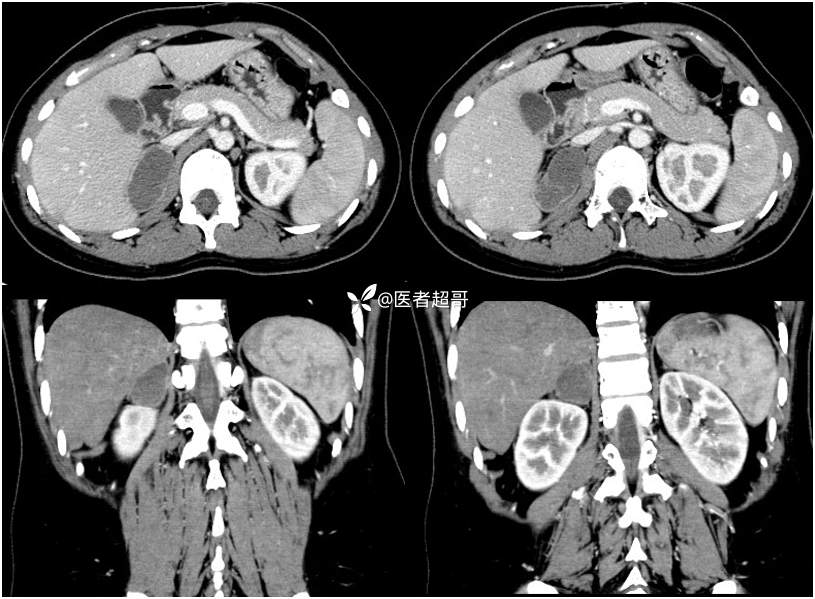

病例【影诊笔记712】女,32岁,体检发现右侧肾上腺占位1年,有病理结果!